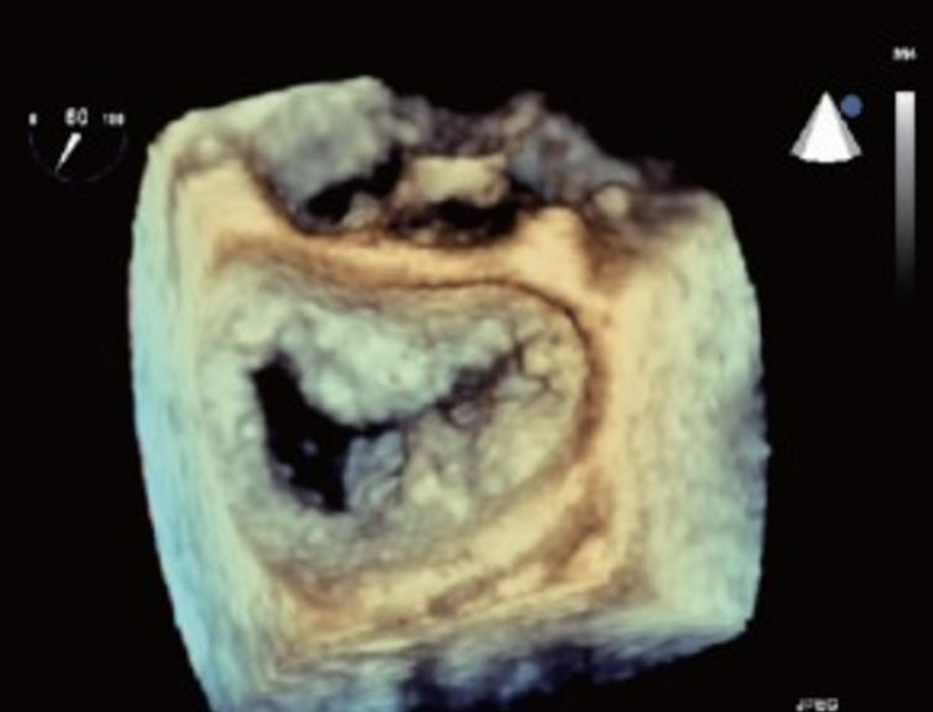

3D of the MV demonstrating?

Flail mitral leaflet